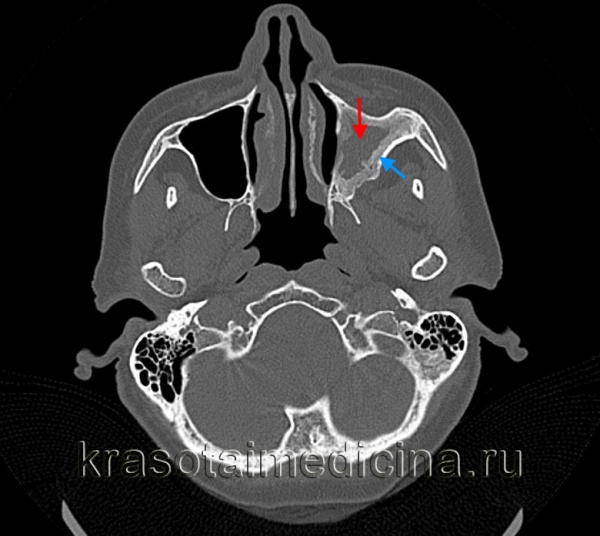

Диагностические методы выявления острого гайморита согласно МКБ-10

Диагноз «острый гайморит» ставится на основании осмотра, риноскопии и жалоб пациента. Опытный доктор сразу скажет, что вы «владелец» гайморита. Для подтверждения диагноза могут быть назначены дополнительные методы диагностики:

- рентгенография верхнечелюстного синуса;

- обзорная рентгенография околоносовых пазух;

- КТ и МРТ;